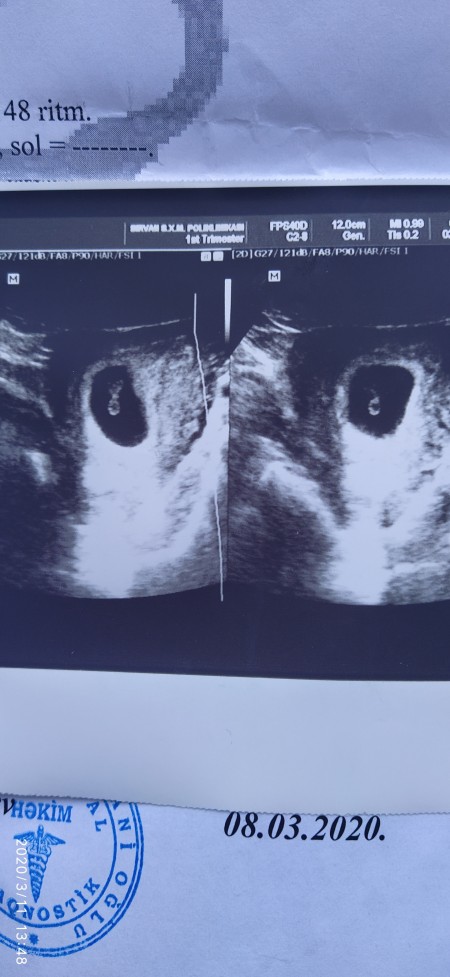

Merhaba . Kizlar bu 7ci hafta ultrason fotoğrafı. Bakinca cinsiyyet tahmini yapa bilirmisiniz ??

Gebelik haftası 7+4

Kese icin diyorsan kiz kesesi gibi yuvarlak

Kiz kesesi gibi kuzum ama doktorun cekis durumunada bagli her ultrasonda yuvarlak cikiyorsa kizdir diyolar ama bilemem tabi gonlunden gecen olsun